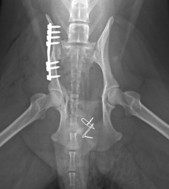

Chirurgia, ortopedia

Wykonujemy szereg zabiegów operacyjnych z zakresu chirurgii miękkiej, jak i twardej. Przeprowadzane przez nas operacje często ratują życie, a niejednokrotnie również polepszają jego jakość.

W ramach chirurgii twardej przeprowadzamy m.in. takie zabiegi jak:

• zwichnięcie stawu biodrowego, w tym resekcja główki i szyjki kości udowej

• operacyjne leczenie złamań i zwichnięć